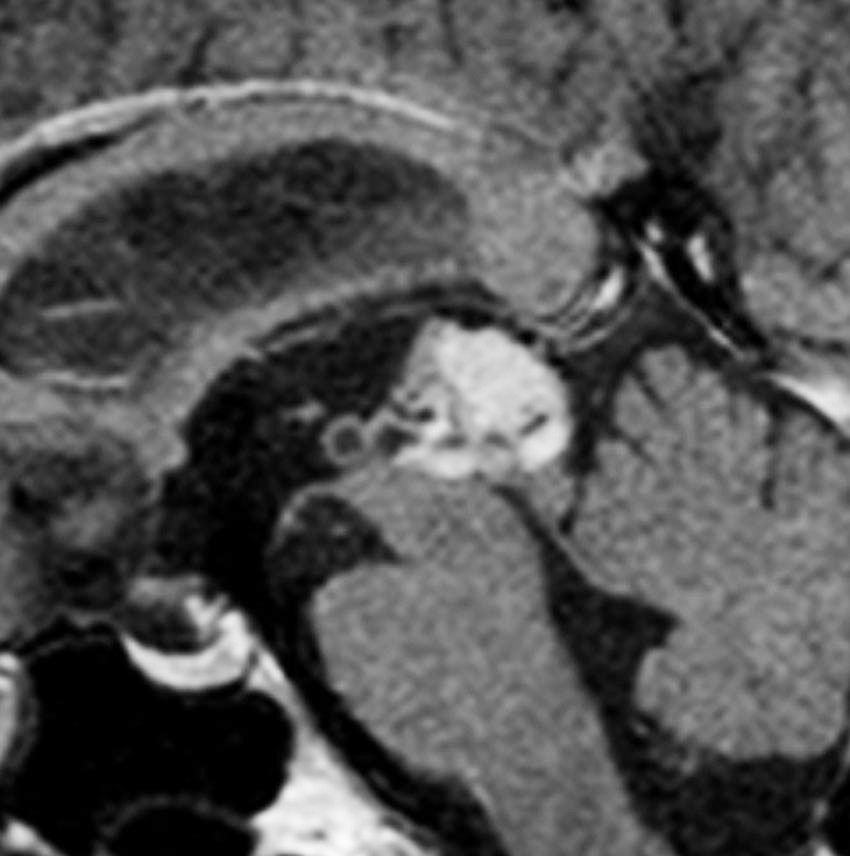

中間型松果体実質腫瘍 PPTID の例3

無症状で発見された40代女性です。1年半の経過観察で増大傾向を示し,閉塞性水頭症となってきました。形が不整形で右視床に食い込んでいるのでPPTIDだと考えて開頭手術をしました。手術所見でも右視床に深く食い込み中脳視蓋の周囲に回り込むように張り付いていました。松果体細胞腫が視床浸潤する事はほとんどなくPPTIDの特徴です。初期の病理確定診断は,PPTID grade II/III (グレード2に近いもの)でしたが,その後,グレード3と訂正されました。グレードが2か3かという判断は,病理診断医にとっても極めて難しいものです。

中間型松果体実質腫瘍 PPTID の例4

水都症で発症した20代の女性です。のう胞を含む境界明瞭な松果体腫瘍で,松果体細胞腫のようにもみえます。しかし,中脳視蓋と左視床に浸潤像が疑われます。OTAで中脳内部に食い込むものも全摘出しました。術後2年で軽度の眼球上転障害を残していますが復職できました。